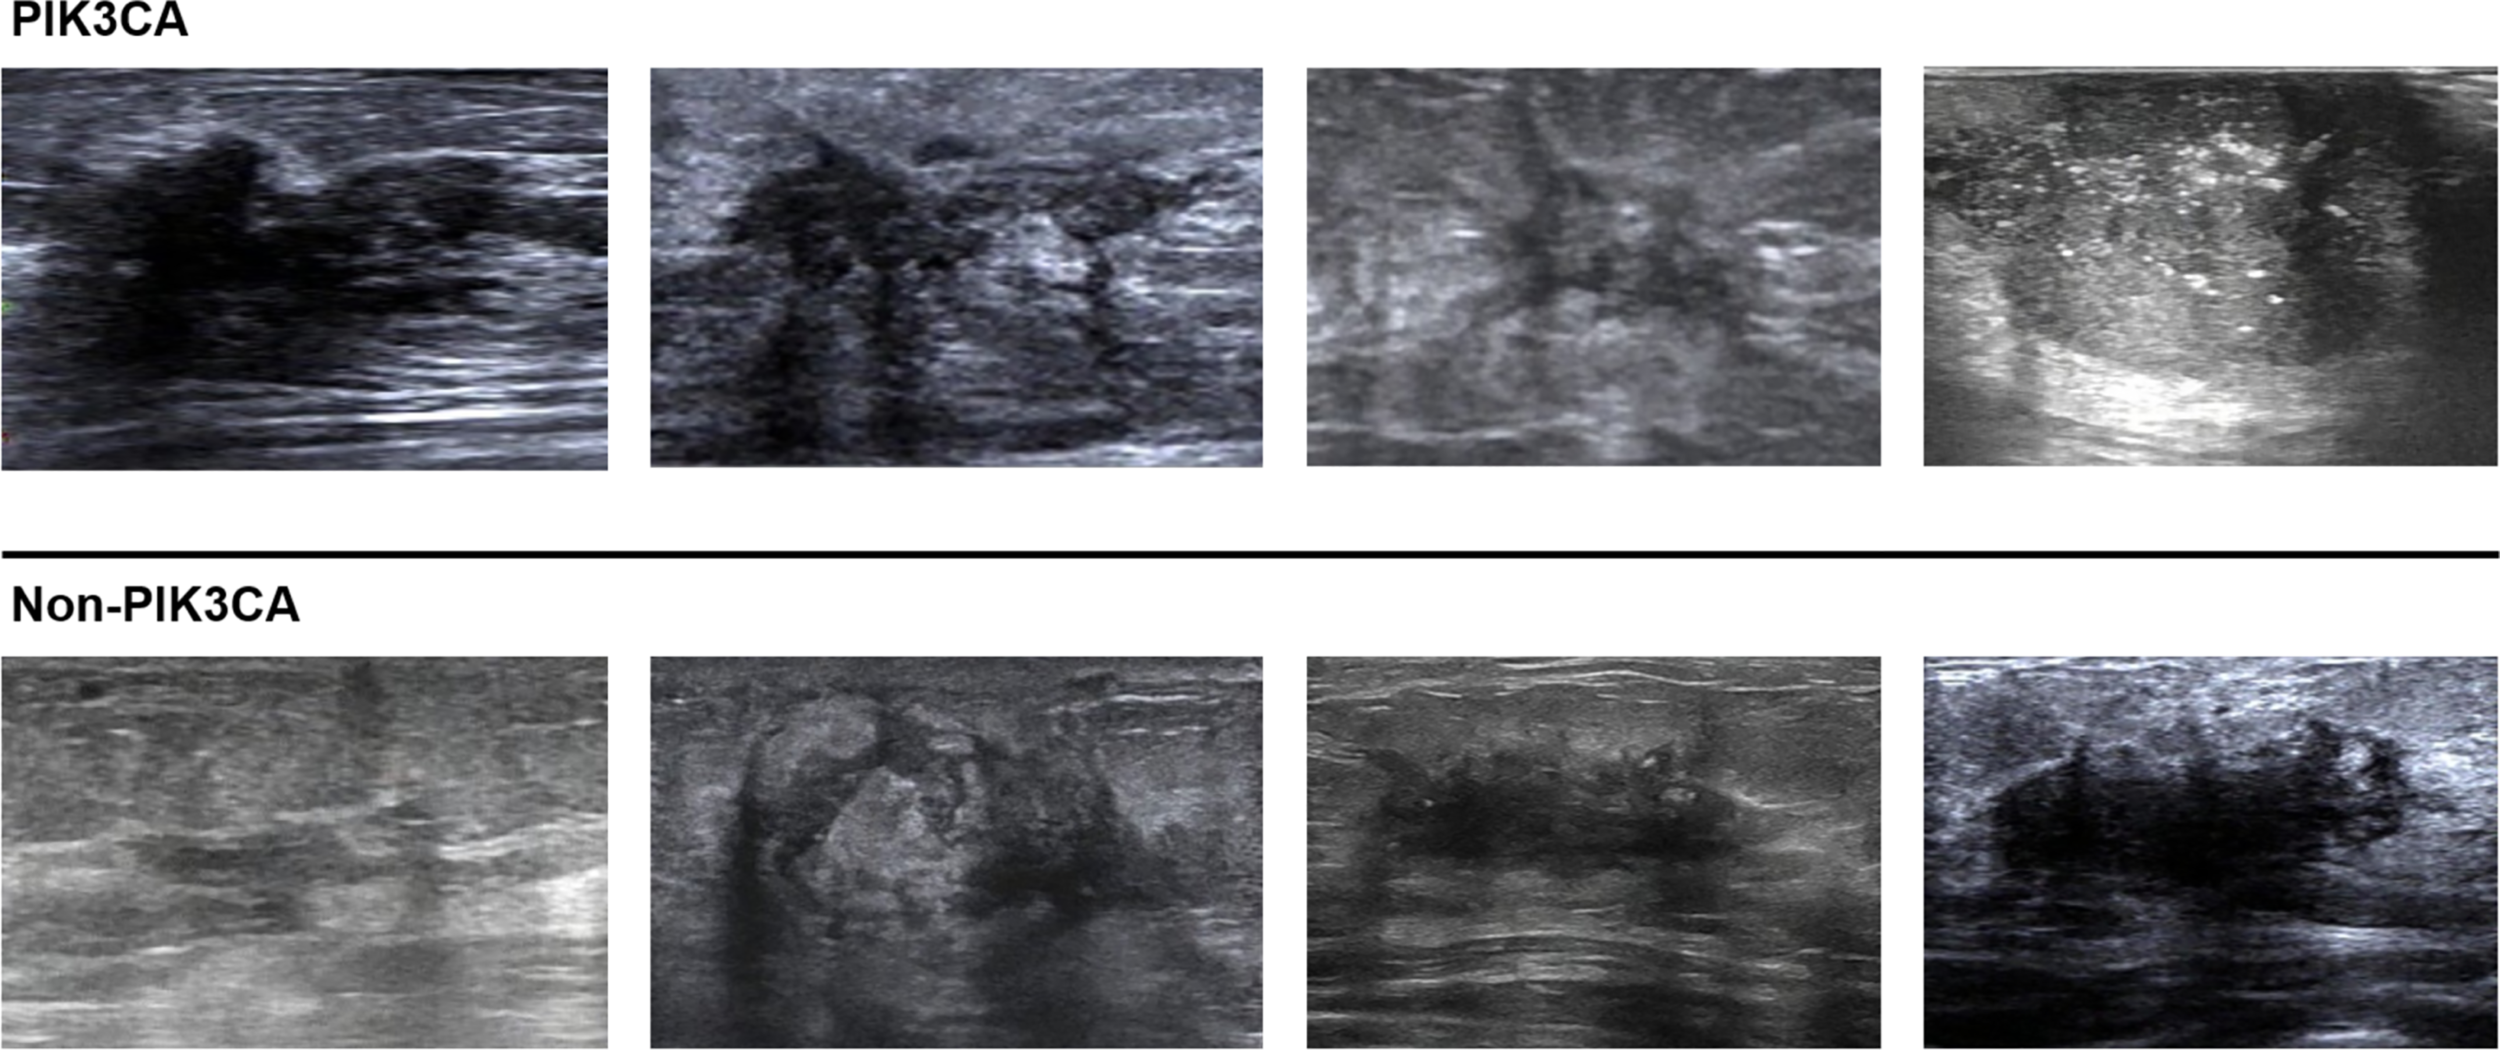

Figure 6

Classification examples of the ImResNet model.

For the test set of 200 US images, the performance of the ImResNet50 model has been given in Table 1. The ImResNet model achieved the best performance in all models, with an overall accuracy of 74.50%, and the average precision, recall, and F1-score reached 73.35%, 74.17%, and 73.60%, respectively. Figure 4A shows the model achieved an AUC of 0.775. Besides, the performance of the ImResNet model can be visualized from the CM in Figure 5. In the figures of CM, the first two rows represent the instances of a predicted class, the first two columns represent the instances of an actual class, the diagonal elements correspond to correctly classified observations, and the off-diagonal cells correspond to incorrectly classified observations. As well, the bottom row is the row-normalized row summary, and it shows the percentages of correctly and incorrectly classified observations for each true class. The rightest column is the column-normalized column summary and displays the percentages of correctly (in green color) and incorrectly classified observations (in red color) for each predicted class. In each cell, the percentage value is calculated using the current number over the whole sample number. Figure 6 shows the classification examples of the ImResNet model. In the first line, the four images in the PIK3CA category are listed, while the four images in the Non-PIK3CA category are shown in the second row.